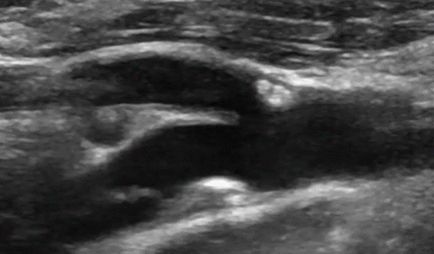

• Триплексное сканирование брахиоцефальных артерий

• атеросклероз внечерепных отделов магистральных артерий головы со стенозом в области каротидной бифуркации слева до 54%.